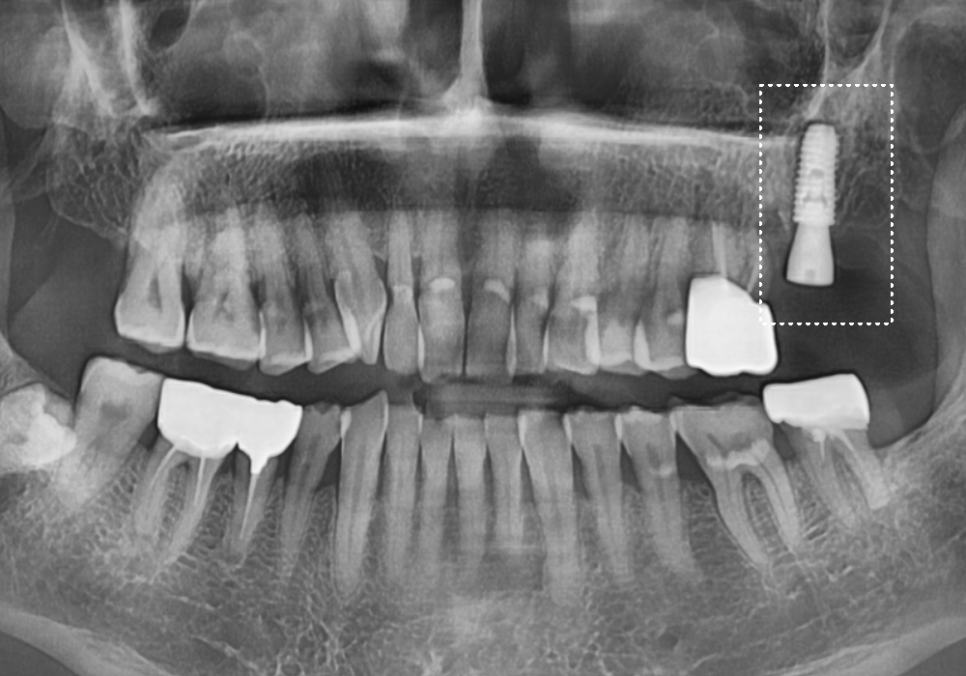

왼쪽 위 어금니 두 개(#26, #27)가 동시에

시큰거려서 내원하셨는데요~

정밀 CT를 통해 분석해 보니,

치아에 금이 가 있는게 보입니다.

앞쪽 어금니(#26)

: 금이 머리 쪽에만 머무른

'치관 파절'로 예후가 좋아 보였지만,

맨 끝 어금니(#27)

: 금이 뿌리 쪽으로 깊게 내려간

'수직 치근 파절' 상태였습니다.